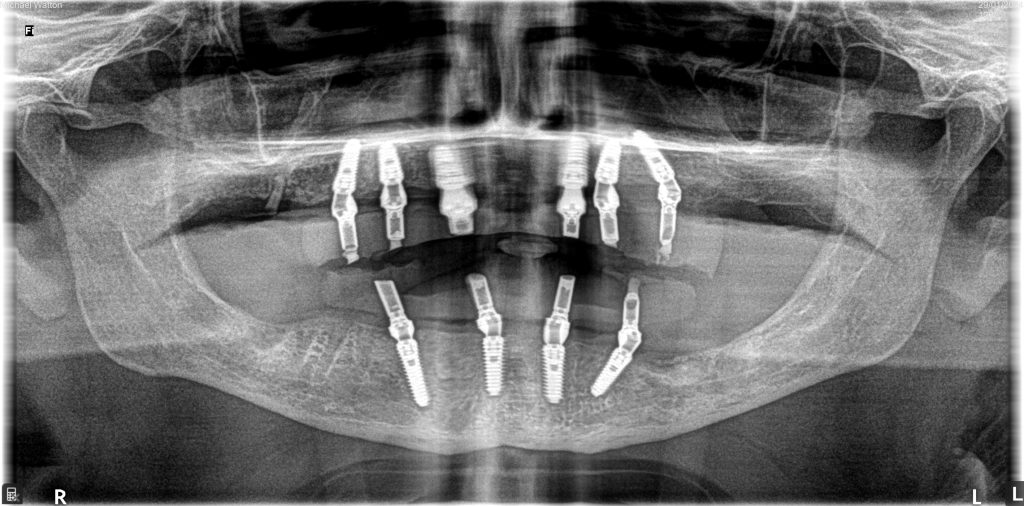

SK: We removed all lower teeth and placed four implants, which we immediately loaded using the skills of our lab technician.

For the upper arch, we removed all upper teeth and provided an immediate complete denture. The plan was created digitally and all records were sent to the lab prior to the surgery.

We left the upper arch for three months, then placed our implants and immediately loaded. We were able to do this in a clean and settled site.